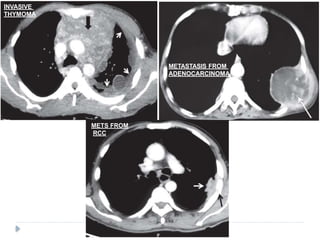

INVASIVE

THYMOMA

METASTASIS FROM

ADENOCARCINOMA

METS FROM

RCC

PLEURAL METASTASES ⚫ Adenocarcinomasare known to cause pleural metastasis than any other histological types of cancers. ⚫ Common primary sites are from : lung, lymphoma, and ovary, invasive thymoma ⚫ Pleural effusion is the most common finding on imaging .